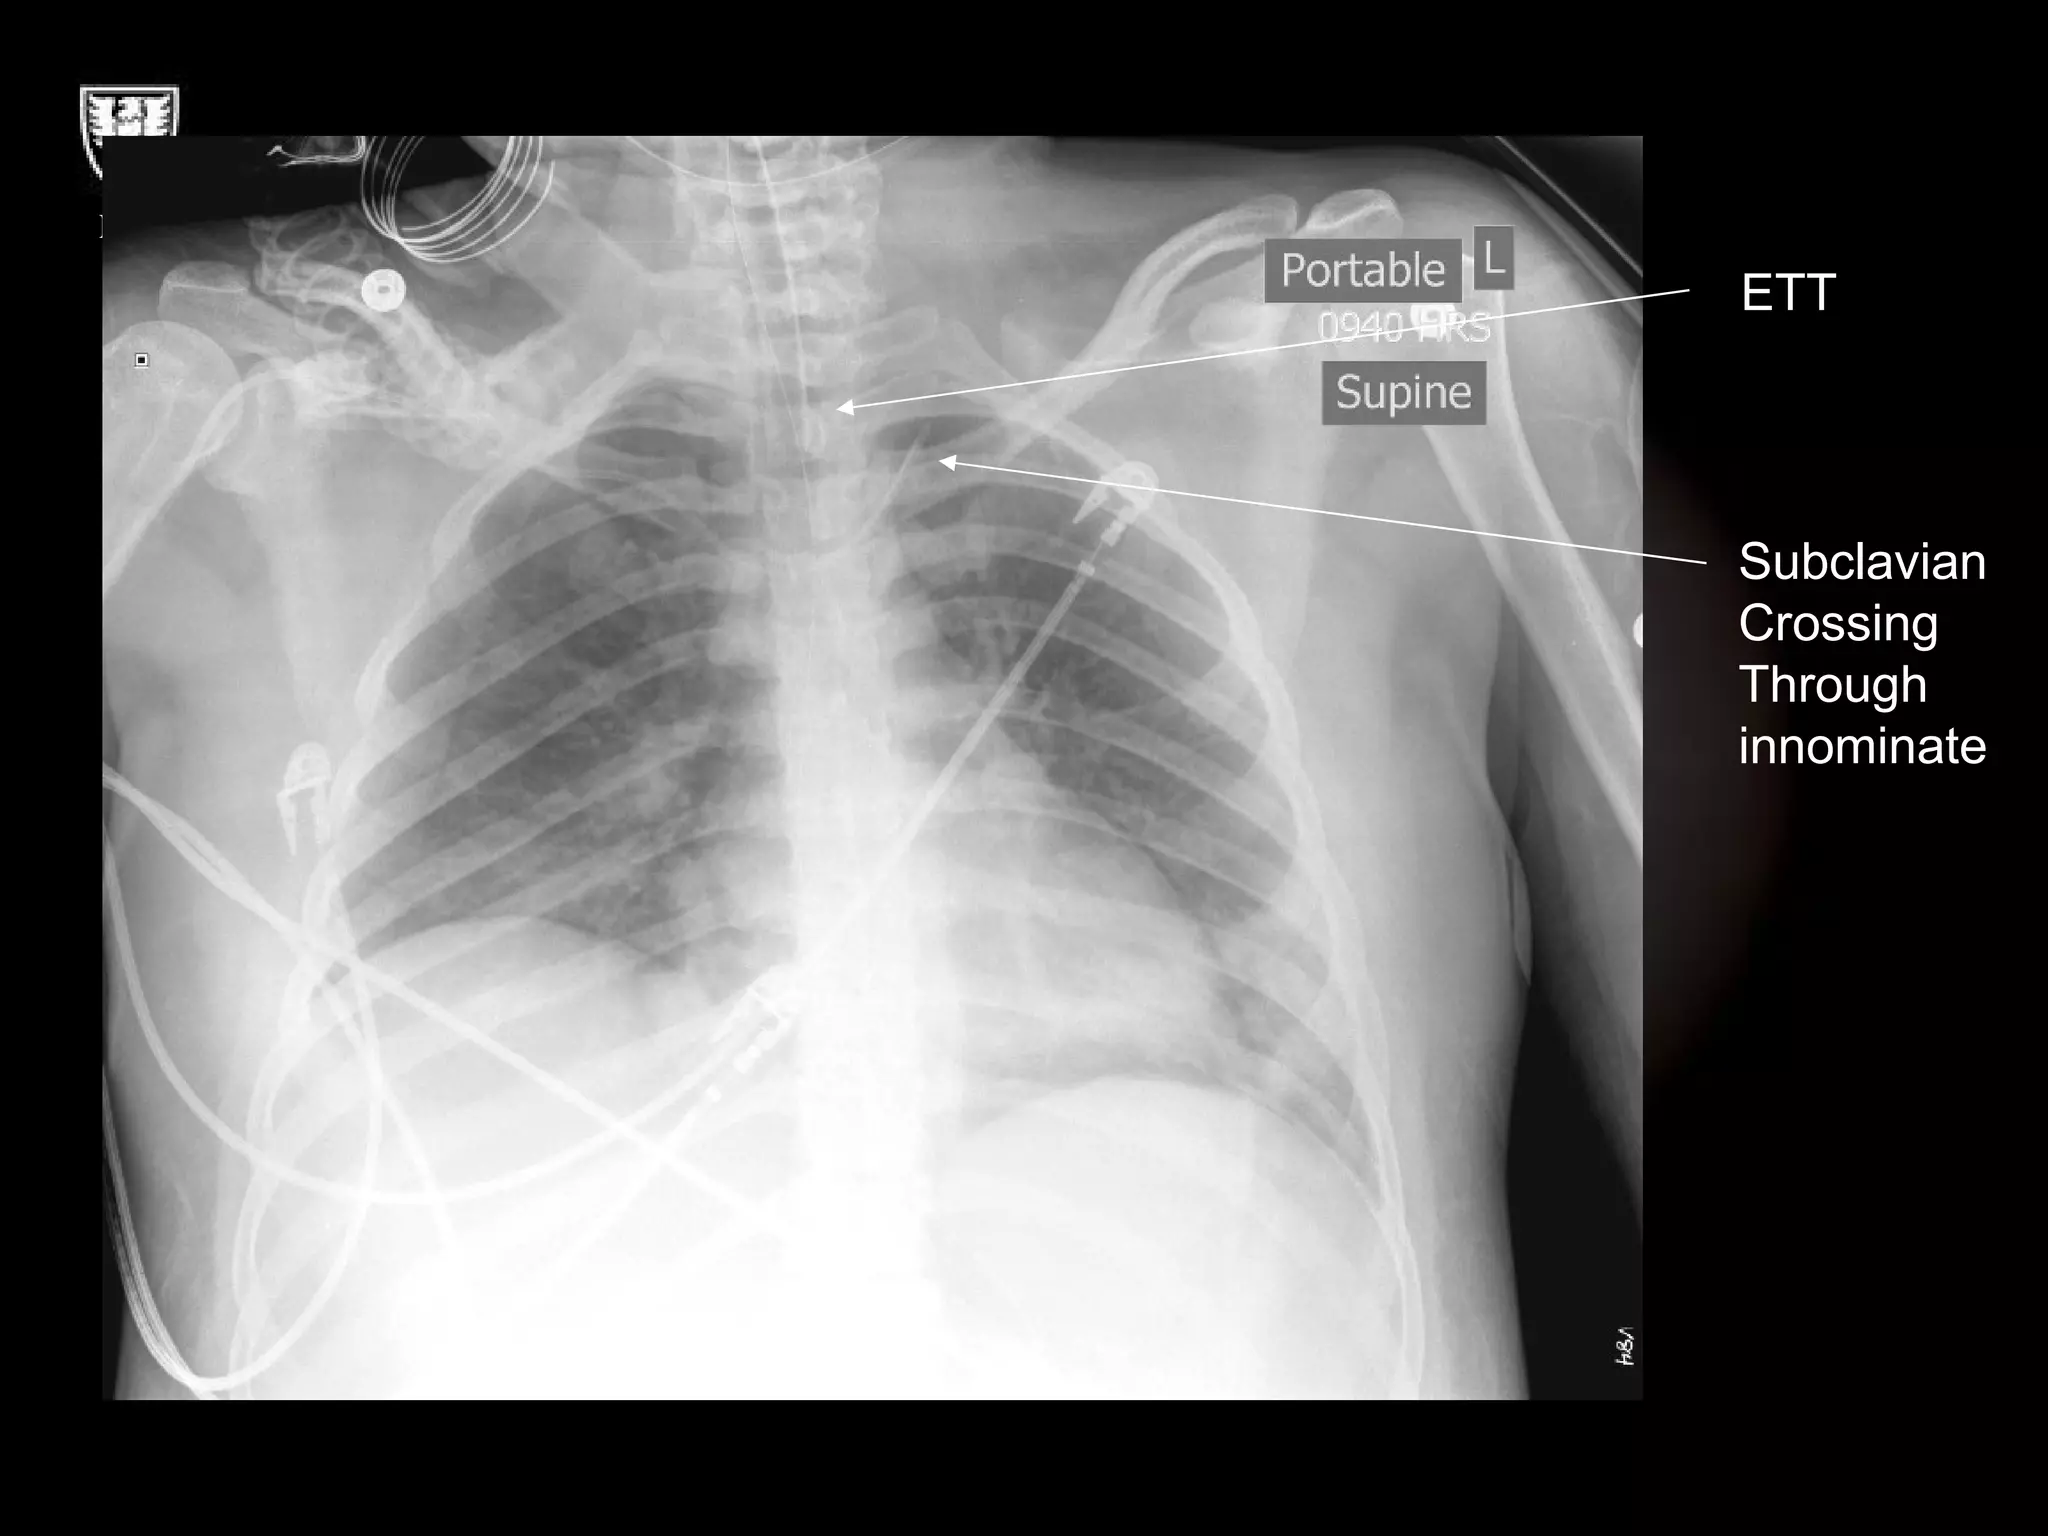

ETT Subclavian Crossing Through innominate

ETT Subclavian CrossingThrough innominate